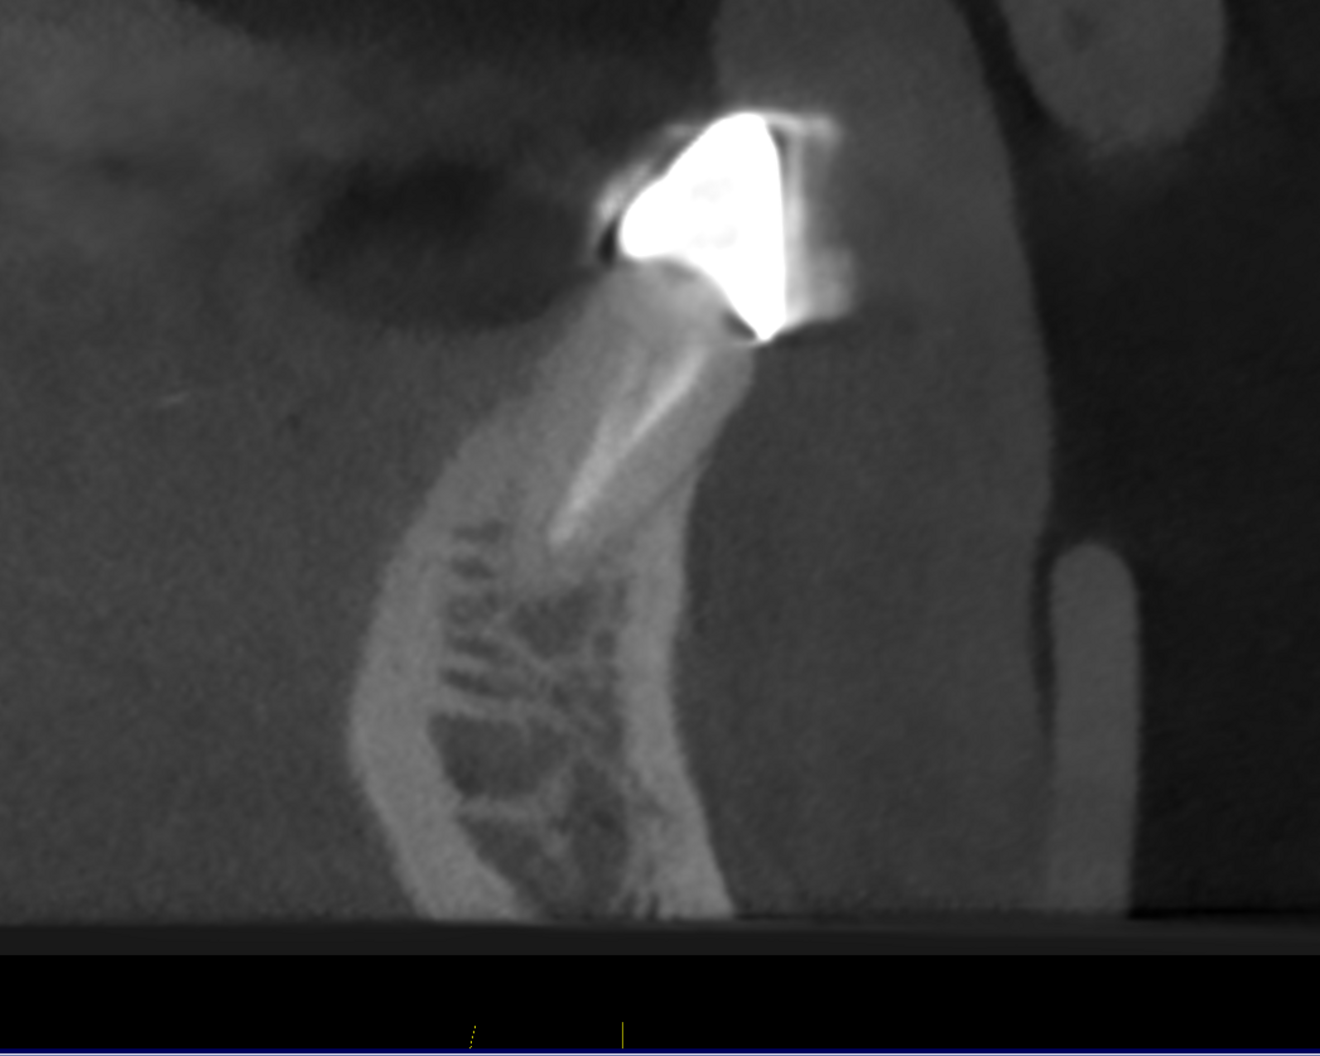

Figs. 2a–c: CBCT scan showing the failing endodontically treated tooth with an abscess.

The patient presented with multiple periapical radiolucencies associated with failing endodontically treated teeth, a horizontal root fracture and a failing long-span bridge (Fig. 1). A poor long-term prognosis was given to all the remaining mandibular teeth except tooth #46 (Fig. 2), and the treatment options, limitations and risks were reviewed thoroughly with the patient. The patient did not want a removable restoration and did not want to go a day without teeth and wanted to have biologically friendly materials used for treatment. It was decided to perform an immediate implant surgery and provide the patient with a stable temporary restoration to protect the healing implants for long-term success.